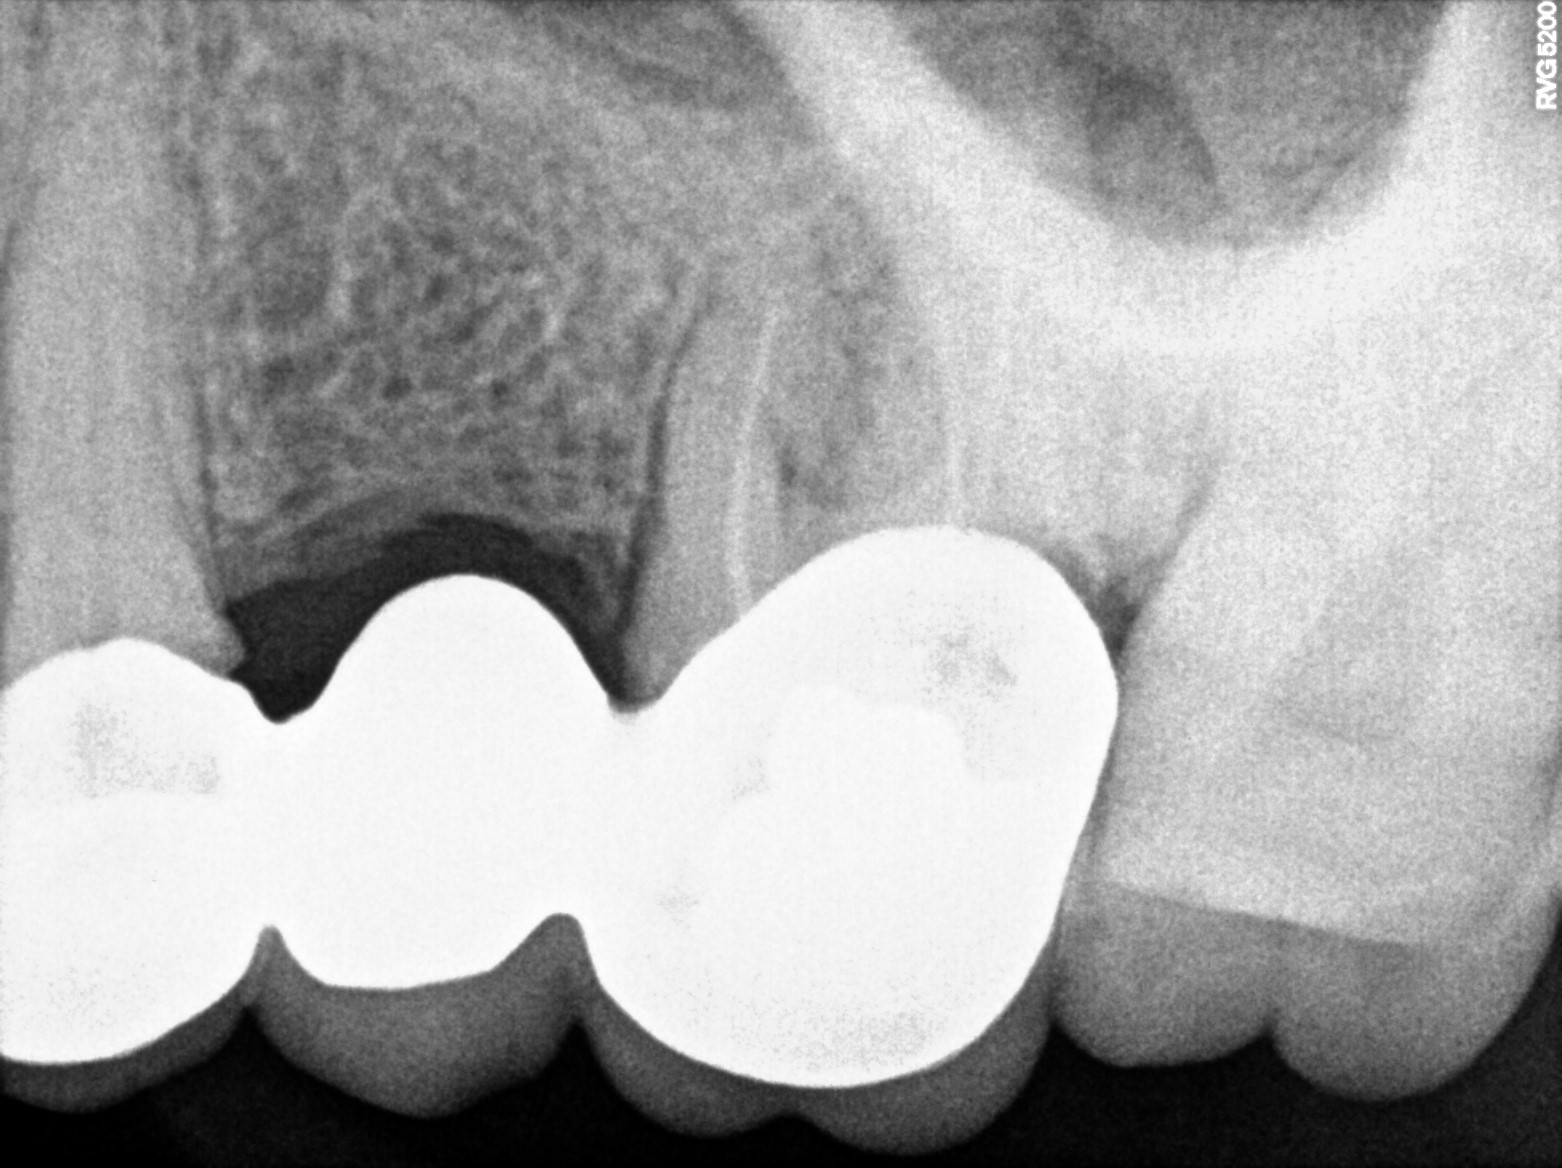

Dental Radiographs FHIR: DocumentReference · LOINC 24641-7

2 (1).jpg

24641-7